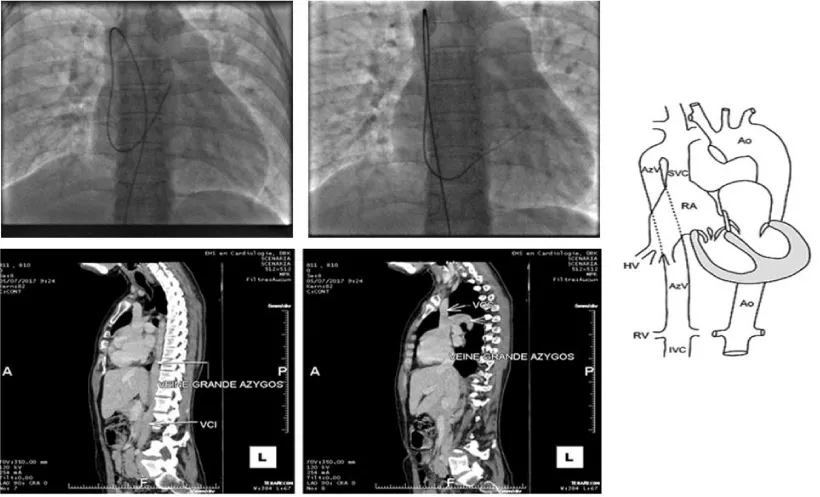

We started the procedure under local anesthesia and femoral vein 6Fr access, we introduced an MPA catheter, which drew an unusual path with a loop behind the right atrium to join the superior vena cava and then the right atrium.

Faced with this trajectory, we suspected an association with an azygos continuation of the inferior vena cava. We interrupted the procedure and requested a CT angiography that confirmed the diagnosis (Figure 2).

Figure 2: Azygos continuation discovered in angiography and CT.